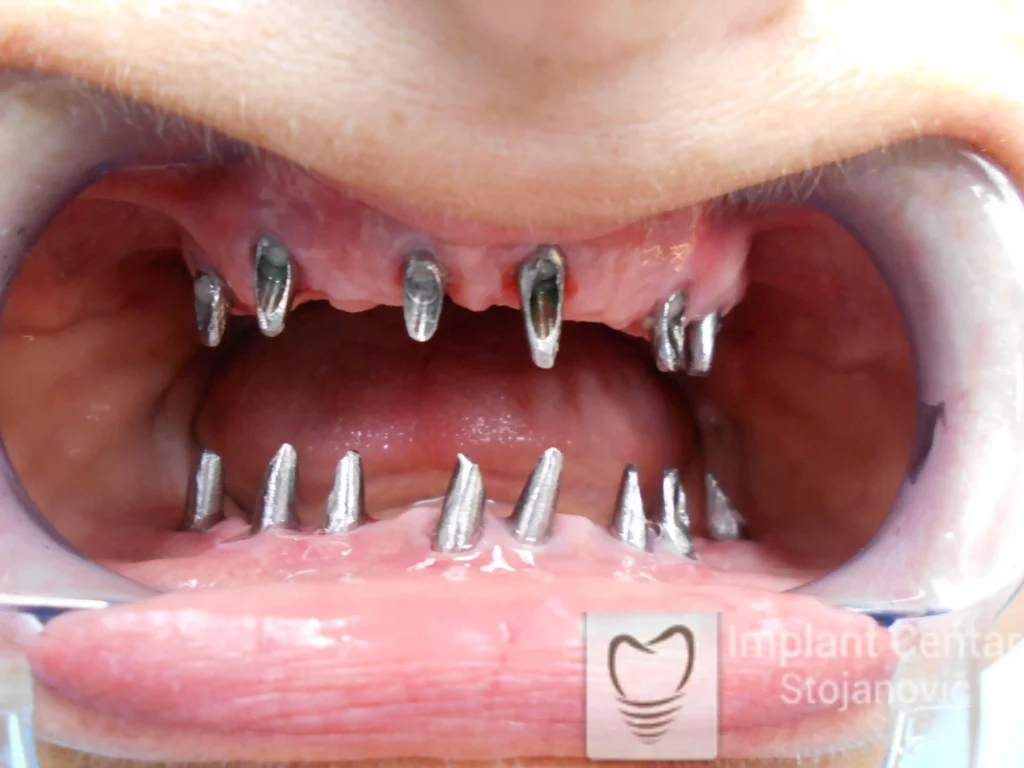

Na slikama 1, 2, 3 , 4  i  5 prikazan je izgled pacijenta pre početka terapije. Nakon detaljne kliničke i radiološke analize, doneta je odluka o vađenju zuba loše biološke vrednosti, dok su bezuba polja sanirana ugradnjom dentalnih implantata.

Nakon ugradnje implantata i pripreme preostalih zuba, pacijentu su izrađene fiksne privremene krunice, čime je postignut eugnatan zagriz već nakon jednog dana (slika 8, 9 i 10). Tokom perioda osteointegracije, pacijent se postepeno privikavao na novi položaj vilica i zagriz.